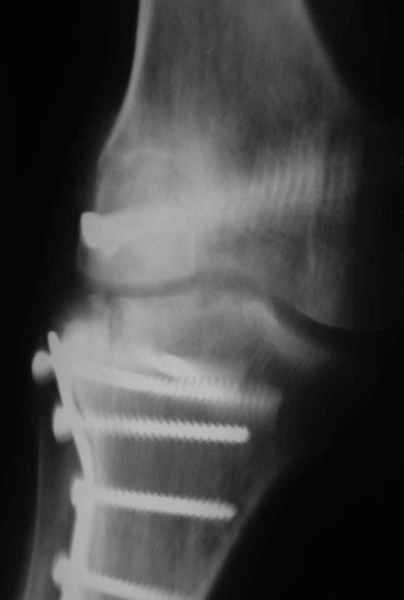

На прием обратилась больная 38 лет. Травма 17.01.2005. 23.01.2005 - операция в одном из стационаров области - остеосинтез мыщелка бедра винтами, Остосинтез мыщелка большеберцовой кости L-образной пластиной.

Остальные снимки Ноябрь 2005

Иммобилизация лонгетной гипсовой повязкой 2 мес. После прекращения иммобилизации, пр начале ЛФК отмечена нарастающая вальгусная деформация конечности. Рентгенограммы в приложении. Хотелось бы узнать Ваши предложения по тактике лечения